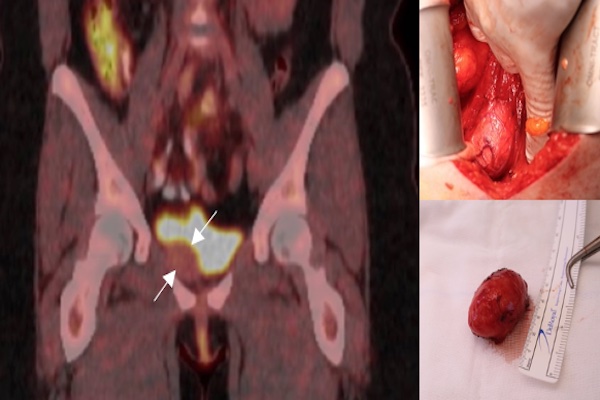

A partial cystectomy was planned with the impression that this lesion was likely intramural and was not sarcomatous. Intra-operatively the mass was noted to be extramural and adjacent to the right inferolateral bladder wall (Fig. 2). The lesion was circumferentially dissected free and partial cystectomy was avoided. Her post-operative recovery was uneventful. Histopathology confirmed leiomyoma with the tissue composed of interweaving bands of bland smooth muscles with no cell atypia.

Figure 2. (A) An intraoperative photo of bladder leiomyoma on cystoscopic evaluation; (B) An intraoperative photo of bladder leiomyoma in situ, attached to bladder wall; (C) Bladder leiomyoma after excision